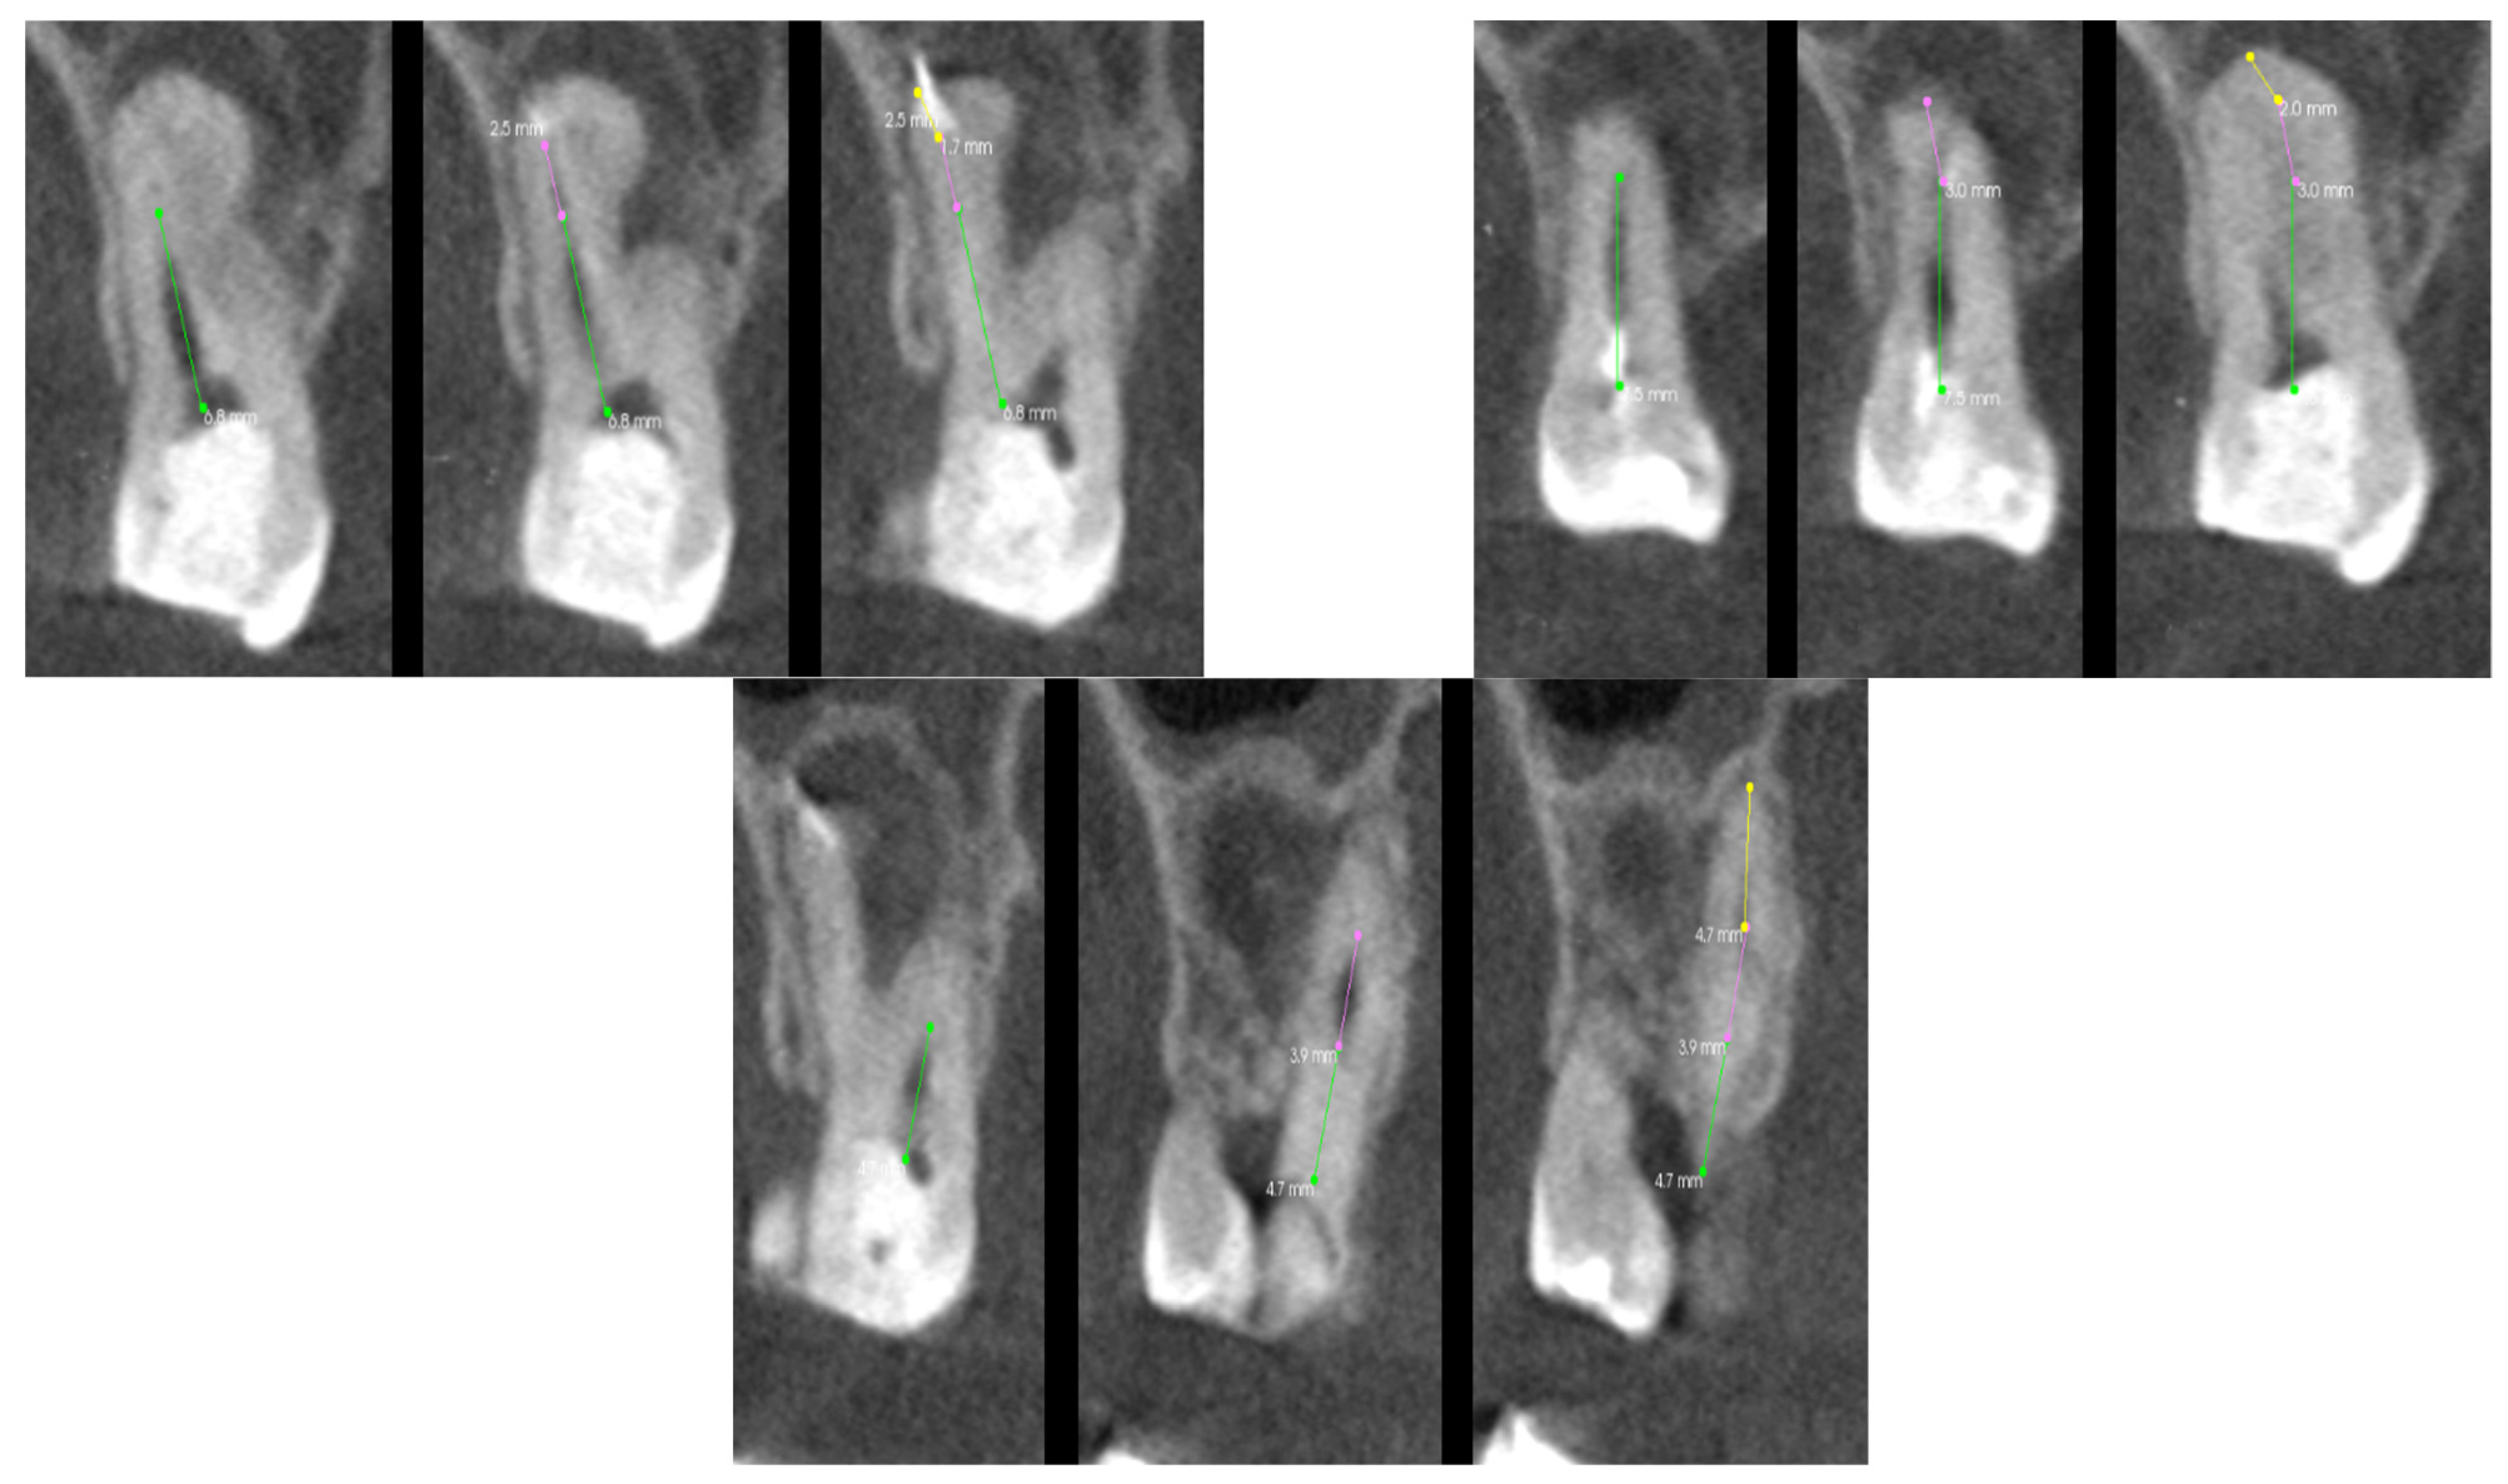

3.5. Case 5—The Treatment of Tooth 46

In this case, the patient was referred for endodontic retreatment of tooth 46 due to incomplete canals and the presence of a broken instrument in the mesial lingual canal. The CT scan of the tooth, which was used for the analysis of the root canals in the transverse plane in the case of tooth 46, is shown in Figure 15. The generated 3D model made it possible to determine the exact position of the tool concerning the lingual tubercle and the number of root tissues surrounding the file, as shown in Figure 16. By determining the location of the proximal end of the broken file, access and visibility in the operating microscope were obtained. Munce burs and ultrasonic tips were used for access. Thanks to the precise location provided by the hologram, access was obtained without unnecessary loss of root tissue, which could lead to perforation or root fracture in the future. The broken file was removed using a Miller needle as an ultrasonic tip. The canals were developed and filled with permanent material. This stage of treatment ended with a traditional X-ray. As in the above cases, the visibility of all root canals in the transverse plane was analyzed on individual scans, which are presented in Table 6.

Figure 15. The CT scan of the tooth was used for the analysis of the root canals in the transverse plane, in the case of tooth 46.

Figure 16. The 3D hologram of tooth 46, subjected to endodontic treatment.